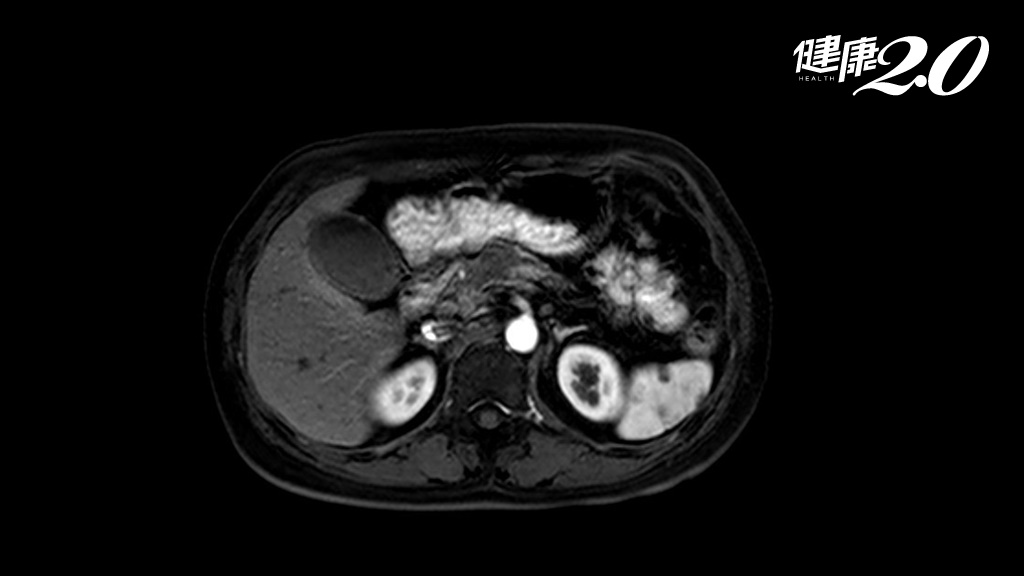

60多歲的男子在健檢時被診斷出大腸癌第3期,經過腸切除和化療,半年內癌細胞轉移到肝臟,進入第4期。醫師建議他癌症治療期間多攝取抗癌食物,如蔬菜可協助抗癌,男子仍拒絕吃蔬菜,只願意每天吃半碗菇類。現在兩年半過去了,男子病情控制良好,也沒有再復發。

腎臟科醫師江守山在節目中分享了這個案例,這名60多歲的男子在健檢時發現罹患大腸癌,已經轉移到淋巴,確診為第3期。經過腸子切除和化療後,半年後癌細胞仍轉移到肝臟,進入第4期。江守山建議他要多吃蔬菜,但男子拒絕,他說「不知道還能活多久,就喜歡吃肉,覺得吃蔬菜像在吃草,每次吃都覺得自己像是一頭羊,所以想隨自己喜歡的吃肉」。

後來江守山想到,根據日本調查,所有職業類別中,「菇農」最不容易得癌症,改提議多吃菇類。男子聽從建議,每天吃了半碗煮熟的菇類,到現在2年半,第4期癌症都沒有再復發。